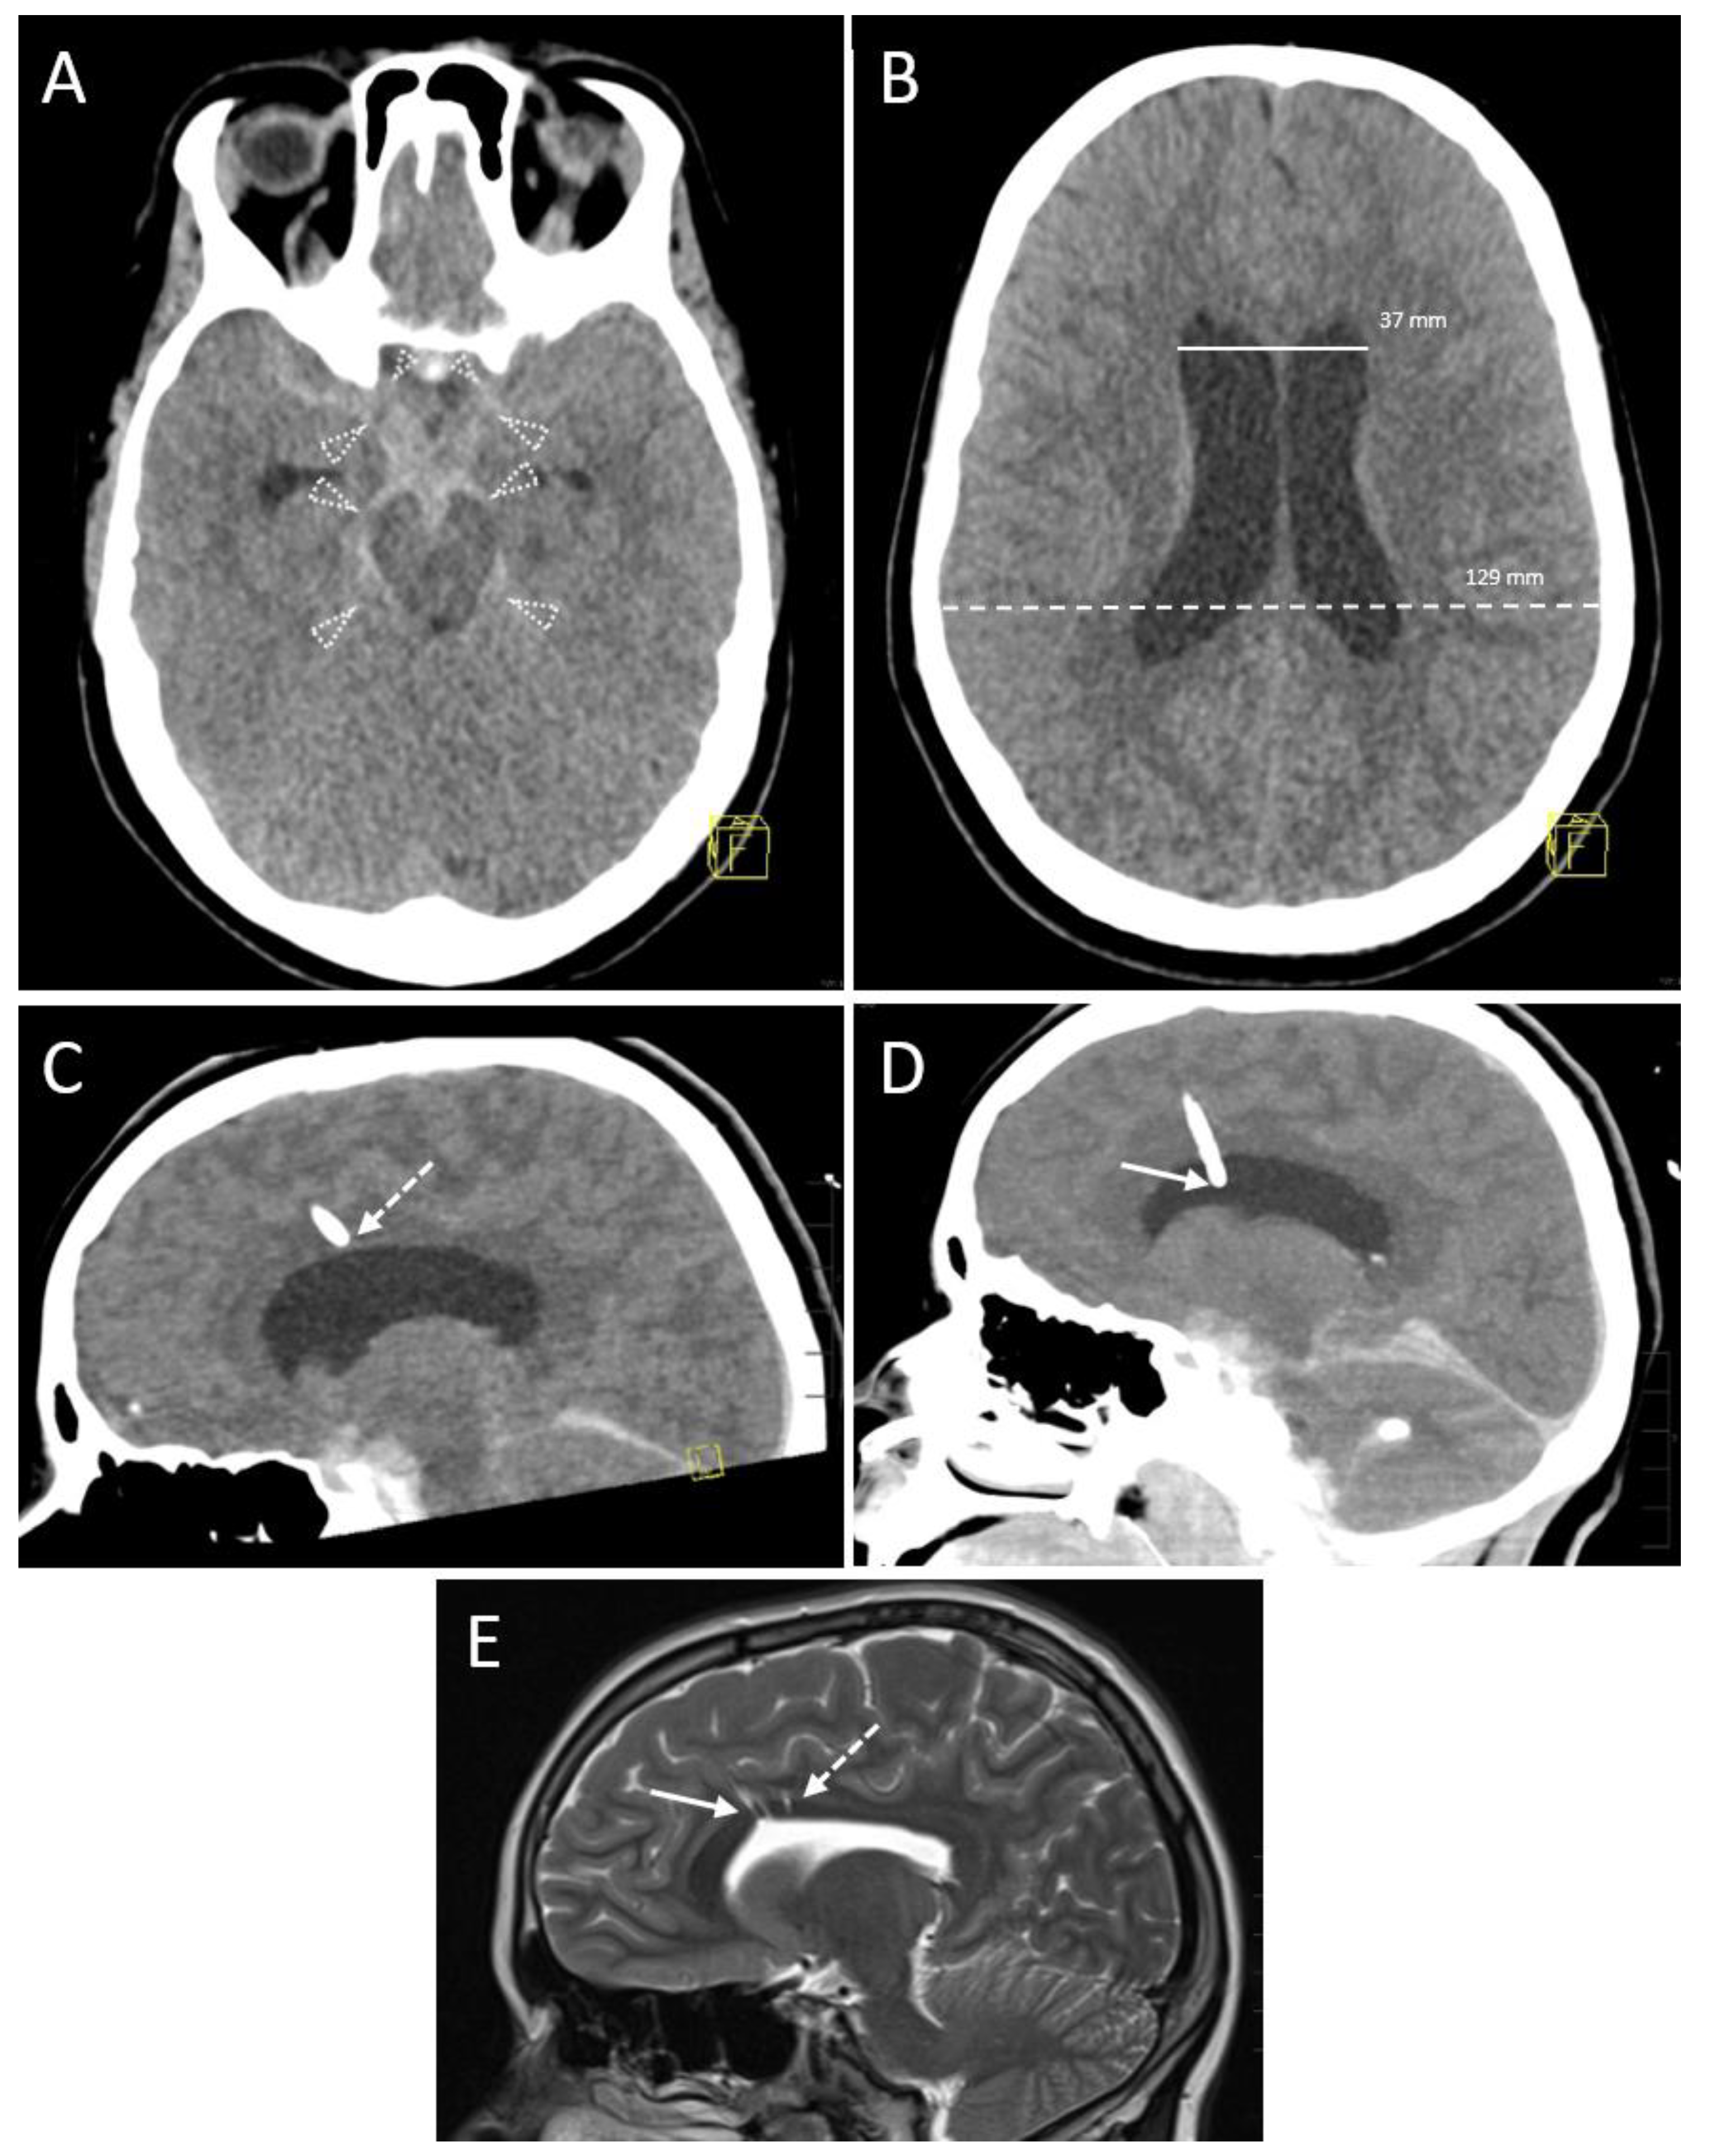

3.2.3. Accuracy

3.2.4. Hemorrhage

| EVD position in 1st control CT scan | |

| Kakarla I | 28 (77.8) * |

| Kakarla II | 8 (22.2) * |

| Final EVD position | |

| Kakarla I | 35 (97.2) * |

| Kakarla II | 1 (2.8) * |

| Hemorrhage on follow-up CT | |

| No evidence of hemorrhage | 32 (88.9) * |

| Grade 1 (<1 mL) | 3 (8.3) * |

| Grade 2 (≥1 to 15 mL) | 1 (2.8) * |

| Grade 3 (>15 mL) | 0 (0.0) * |